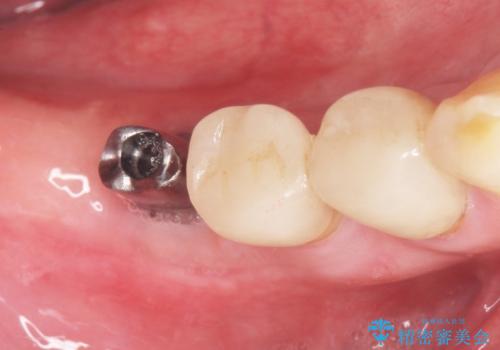

- 奥歯の違和感を主訴に来院された患者様です。

精査したところ、右下の奥歯は大きなう蝕により保存不可能な状態でした。

患者様のご希望により、抜歯後インプラント治療を行いました。